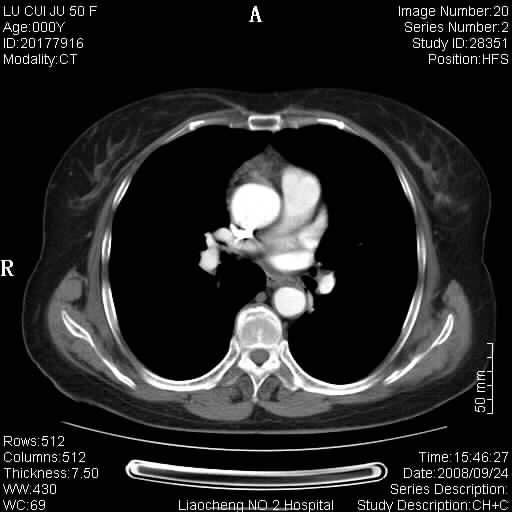

标题: CT15870:F50Y,纵膈占位,是不是胸腺瘤,请各位高手讨论。

临床表现为重症肌无力;ct增强扫描可见前纵膈胸腺部位弥漫性簇状软组织节结灶,不知道是不是胸腺瘤,请各位高手讨论。

考虑胸腺增生

考虑胸腺增生!!